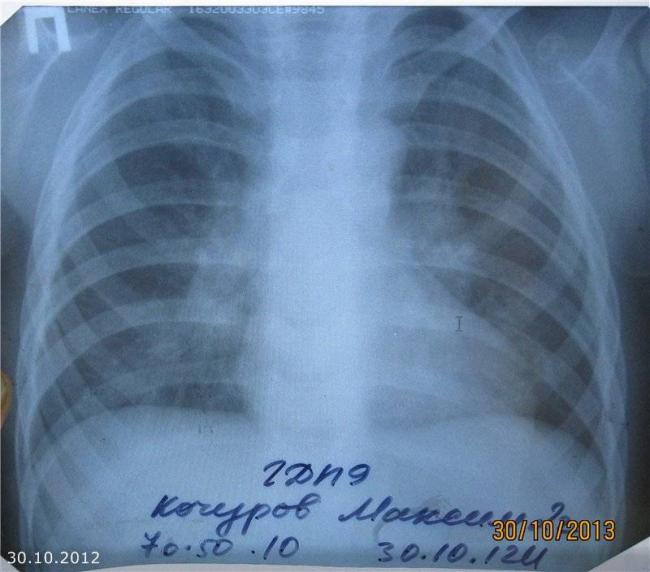

Основным методом диагностики прикорневой пневмонии являются рентгенологические методы исследования. На рентгенограммах врач может увидеть локализацию воспаления, дифференцировать прикорневое воспаление лёгких от других заболеваний дыхательных путей. Но при прикорневой пневмонии интерпретация рентгенографического исследования может быть затруднительной. Затемнение от воспалённого очага часто наслаивается на корень лёгкого. В результате легочный корень на рентгеновском снимке «расширяется», что может указывать на новообразование или туберкулёз.

Наиболее точным методом диагностики прикорневой пневмонии является компьютерная томография. Она позволяет более точно определить состояние бронхов и легочной ткани, лимфатических узлов, увидеть неоднородную структуру тени. Для того чтобы определить возбудитель и его чувствительность к антибактериальным препаратам, проводят исследование мокроты.